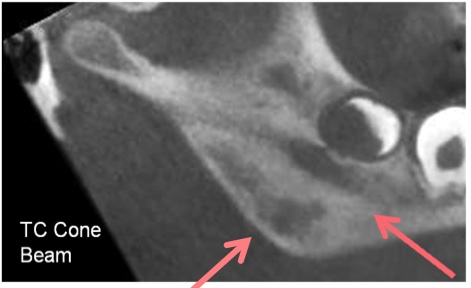

Dopo circa 2 mesi di remissione C. ha ricominciato a presentare saltuario dolore alla caviglia sinistra, con incostante limitazione funzionale, per cui ha ricorso alla terapia antinfiammatoria al bisogno. Inoltre da alcuni mesi ricomparsa di dolore e tumefazione in sede mandibolare destra. Al controllo, per il persistere della sintomatologia, si decide di ripetere la RMN del massiccio facciale che conferma l�interessamento del massetere ed evidenzia un possibile coinvolgimento osseo (Figura 1). C. ha cos� eseguito una TC che ha mostrato un disomogeneo addensamento della trama ossea in corrispondenza della branca montante e dell�angolo mandibolare di destra con qualche areola con aspetto erosivo superficiale del profilo dell�osso, in parte sfumato (Figure 2 e 3). Gli aspetti clinico e radiologico hanno deposto per un quadro di tipo infiammatorio da osteomielite cronica asettica.

Figura 1. RMN del massiccio facciale.